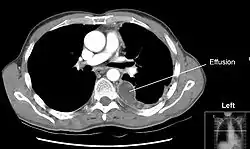

Chest computed tomography is more accurate for diagnosis and may be obtained to better characterize the presence, size, and characteristics of a pleural effusion. Lung ultrasound, nearly as accurate as CT and more accurate than chest X-ray, is increasingly being used at the point of care to diagnose pleural effusions, with the advantage that it is a safe, dynamic, and repeatable imaging modality.[11] To increase diagnostic accuracy of detection of pleural effusion sonographically, markers such as boomerang and VIP signs can be utilized.[12]

CT scan of the chest showing a left-sided pleural effusion. The fluid usually settles at the lowest space due to gravity; in this case, at the back because the patient is supine.- The lung expanding within an area of pleural effusion as seen by ultrasound